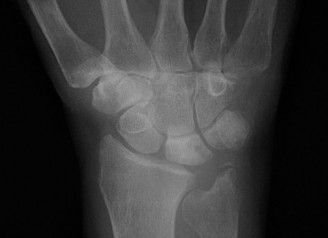

CASE 1 ### A 14-year-old patient presents with pain in the wrist after a fall. Examination reveals tenderness over the anatomical snuff box. X-ray picture is shown below (Fig. 3–1). What is the next course of treatment?

Figure 3–1(©) Sunil Thirkannad and Christine M. Kleinert.

The correct answer is (D). Injuries to the wrist with tenderness over the anatomical snuff box should raise the suspicion of a scaphoid fracture. Often, a scaphoid fracture may not be visible on initial x-ray pictures. It is prudent in such cases to suspect an “occult scaphoid fracture” and treat the patient in a splint. A repeat x-ray taken 2 to 4 weeks later can often reveal a fracture.